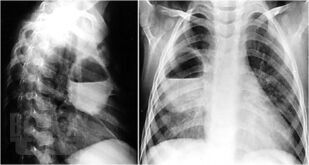

Нагноительные заболевания легких и плевры

В учебном пособии изложены основные варианты нагноительных заболеваний легких и плевры. Дана характеристика, включая этапы развития хирургии нагноительных заболеваний легких и плевры. Приведена классификация, этиология, патогенез каждого патологического процесса. Описаны современные методы диагностики и принципы хирургического лечения. Пособие предназначено для самостоятельной работы студентов лечебного и педиатрического факультета.